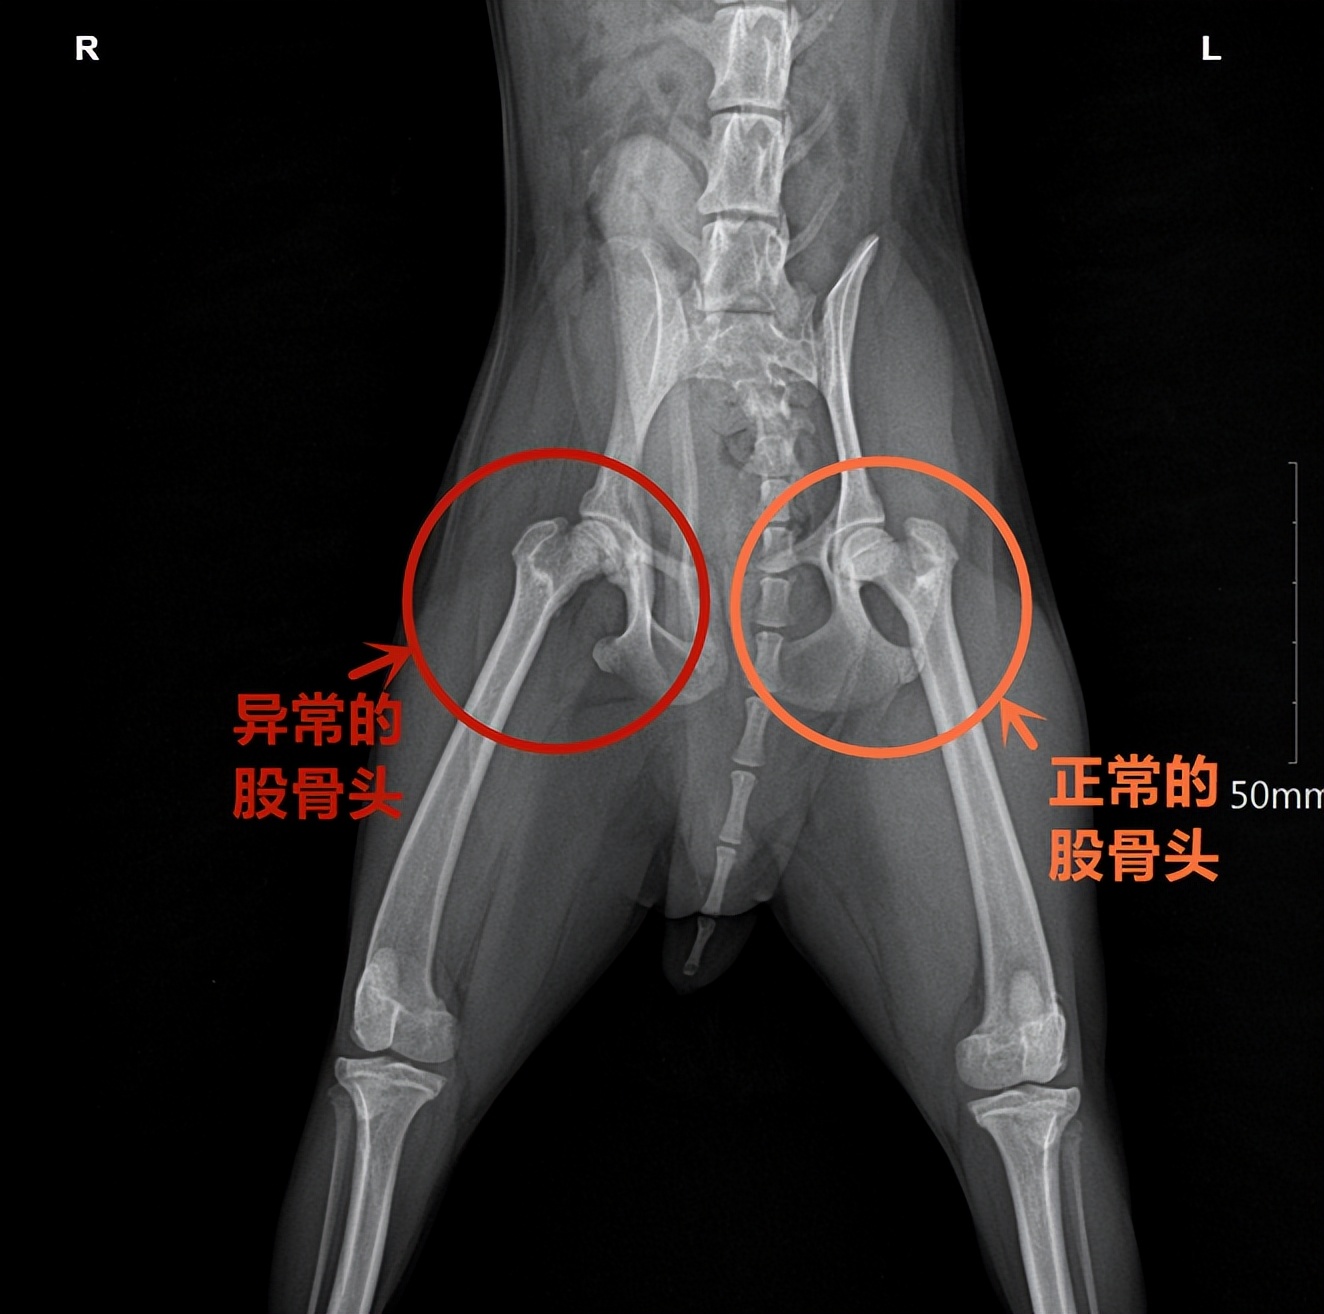

情况不对劲,家长立马带着小贵宾来到瑞鹏坂田分院,找到潘文医生。潘医生给狗狗检查完后发现,狗狗后肢两侧股骨头明显不对称,右后肢股骨头表面不平滑、密度不一致,生长板结构消失。

两侧股骨头明显不对称,右侧骨骼畸形,骨骺内骨密度下降

综合所有检查结果,潘医生确诊狗狗得了右侧股骨头缺血性坏死。